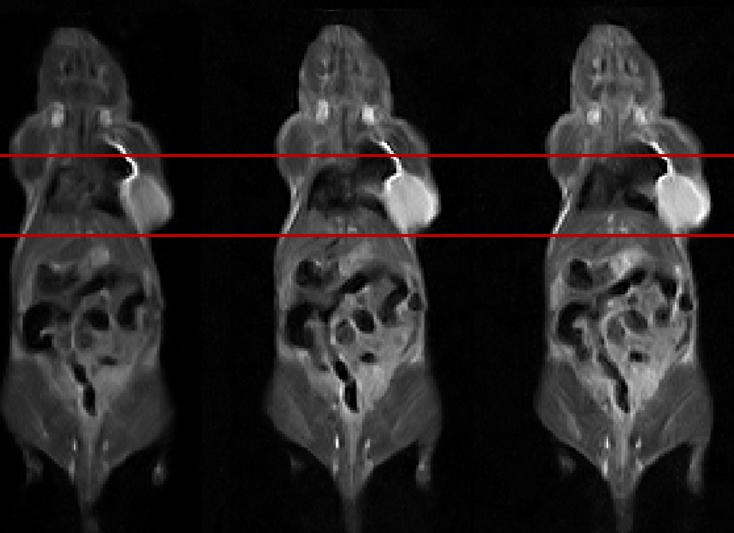

Исследование проводят при подозрении на патологии в тканях или новообразования. С помощью МР-томографии можно провести дифференцированную диагностику новообразований, отличить доброкачественную опухоль от злокачественной. МРТ позволяет выявить кровотечения в малом тазу, камни в желчном пузыре или желчевыводящих протоках. Этот метод диагностики позволяет контролировать органы брюшной полости и сосуды при планировании операции или пересадке органов.

Этот метод исследования позволяет выявить жидкие образования почечной паренхимы. МРТ назначают, когда другие способы диагностики (УЗИ или КТ) неэффективны или рентгенологические исследования противопоказаны. Кроме того, МР-томографию проводят, чтобы контролировать состояние пациента во время лечения болезней почек. МРТ забрюшинного пространства – это эффективный метод диагностики, который позволяет дифференцировать злокачественные и доброкачественные образования в надпочечниках с помощью программ жироподавления.

МРТ забрюшного пространства чаще всего проводят без применения контрастного раствора. Но иногда контрастирование используется, чтобы выявить опухоли почек и надпочечников.

МРТ брюшной полости с контрастом

В некоторых случаях гастроэнтеролог назначает МР-томографию брюшной полости с контрастом. Это необходимо при подозрении на серьёзные болезни, когда без точной диагностики просто не обойтись. Подобное исследование назначают при новообразованиях внутренних органов, чтобы определить вид опухоли. МРТ с контрастом позволяет выявить метастазы в животе, чтобы провести операцию или просто для диагностики. С помощью исследования выявляют тромбы, закупоренные участки в кровеносных сосудах. МРТ с контрастированием позволяет обнаружить микрообразования в надпочечниках, желчных путях, почечных лоханках и других маленьких органах.